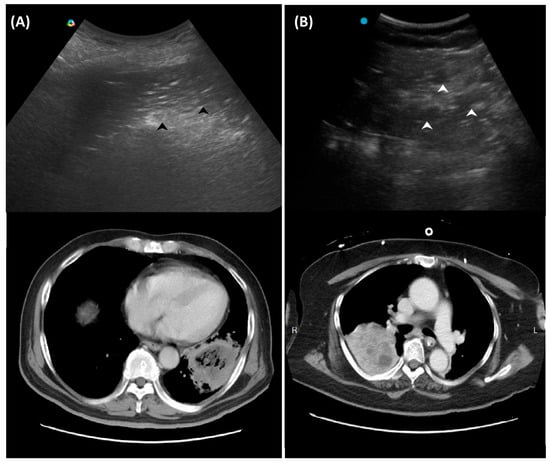

2.1. Red Flag Signs Related to ARDS

Several LUS signs, based on previous studies, indicate a more severe pneumonia, such as acute lung injury or acute respiratory distress syndrome (ARDS). A landmark study sought to differentiate acute pulmonary edema (APE) from ARDS by LUS. Although B-lines (alveolar-interstitial syndrome) prevailed 100% in both APE and ARDS, absence or reduction of the pleural gliding (sliding) was consistently reported in ARDS and rarely observed in APE. ‘Spared areas’ within confluent B-lines were observed in 100% of patients with ARDS and in 0% of patients with APE [21]. In addition, pleural line abnormalities, including irregularity or thickening, were observed in 100% of patients with acute lung injury/ARDS (Figure 1). These signs are classified as level-B evidence, with strong recommendations in a landmark LUS guideline [22].

Figure 1. Pleural irregularity and thickening (arrows) in a patient with acute respiratory distress syndrome.